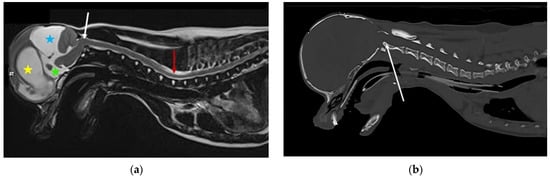

Many small breed dogs are predisposed to Chiari-like malformation, and may have magnetic resonance imaging (MRI) evidence of brachycephaly with hindbrain herniation. However, dogs with signs of pain have more extreme brachycephaly with craniofacial and occipital bony tissue reduction [34,75]. The reduction in the rostral cranial fossa results in rostrotentorial crowding, giving the rostral forebrain a flattened appearance with reduced ventrally displaced olfactory bulbs. The caudal fossa is reduced rostrally by the displaced forebrain and caudally by a short vertical supraoccipital bone. Some dogs have comparatively big brains [76,77]. The cerebellum is flattened against the supraoccipital bone, resulting in vermal indentation and herniation into or through the foramen magnum (Figure 5). The mechanism of the pain is controversial. The most logical mechanism is by obstruction of CSF pathways and reduced intracranial compliance, however, pain may be maintained by a maladapted trigeminocervical complex [78,79].

Figure 5.

Two-year-old female Cavalier King Charles spaniel with Chiari-like malformation and syringomyelia. (a) T2-weighted mid-sagittal brain MRI. There is rostrotentorial crowding, giving the rostral forebrain a flattened appearance (blue arrow), with reduced size and ventrally displaced olfactory bulbs (pink arrow). The caudal fossa is reduced rostrally by the displaced forebrain and caudally by a short vertical supraoccipital bone (yellow arrow). The cerebellum is flattened against the supraoccipital bone, resulting in caudal vermal indentation and herniation into or through the foramen magnum (red arrow). (b) T2-weighted mid-sagittal cervicothoracic spinal MRI showing cerebellar vermis herniation (red arrow). There is wide syringomyelia in the cervical (green star) and thoracic (orange star) spinal cord. This dog was presented with signs of pain and fictive scratching (images created by C. Rusbridge and S.P. Knowler).

Syringomyelia describes spinal cord cavitation (syrinx) with fluid similar to CSF [80]. Syringomyelia is associated with obstruction of CSF pathways, and has been reported in a variety of disorders ranging from intracranial masses to spinal arachnoid diverticulum. However, in veterinary medicine, by far the most common cause is associated with Chiari-like malformation. A small syrinx may not be associated with clinical signs. Large syringomyelia may cause signs of pain, scoliosis, weakness, and ataxia [74]. In dogs, a large syrinx in the mid cervical region that extends to the superficial dorsal horn may have signs of fictive scratching (Figure 5) [81].